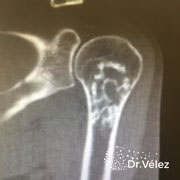

¿Qué es un tumor de células gigantes?

El tumor de células gigantes (TCG) son tumores poco comunes.

Suelen aparecer en diferentes localizaciones del cuerpo, pero suelen tener más incidencia en los extremos de los huesos largos y en la articulación de la rodilla.

Según la OMS (Organización Mundial de la Salud), está clasificado como una lesión agresiva y potencialmente maligna debido a su evolución impredecible. No obstante, el 80% de los casos tienen un curso benigno.

Dependiendo del grado de aparición histológico de las células estromales y el número de células gigantes y mitosis, los tumores de células gigantes se clasificaran como: Benignos, agresivos o malignos.

¿Cómo se diagnostica?

Para diagnosticarlo, su médico realizará una exploración física, y puede

solicitar las siguientes pruebas de imagen:

• Radiografías

• Tomografía computarizada (TAC)

• Resonancia magnética

• Gammagrafía ósea